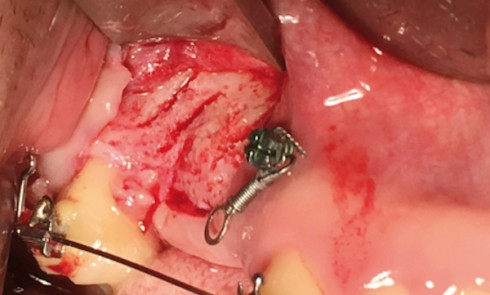

Article réservé à nos abonnés Parodontite sévère : quand l’orthodontie et les traitements biomimétiques redonnent le sourire

Les maladies parodontales entraînent des destructions irréversibles des tissus muqueux et osseux, qui peuvent avoir d’importantes répercussions esthétiques et altérer...